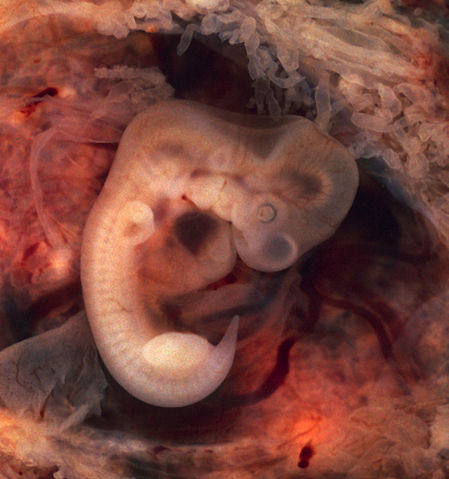

Human Embryo (7th week of pregnancy, 5th week p.o.) This photo of an opened oviduct with an ectopic pregnancy features a spectacularly well preserved 10-millimeter embryo. It is uncommon to see any embryo at all in an ectopic, and for one to be this well preserved (and undisturbed by the prosector's knife) is quite unusual.

Even an embryo this tiny shows very distinct anatomic features, including tail, limb buds, heart (which actually protrudes from the chest), eye cups, cornea/lens, brain, and prominent segmentation into somites. The gestational sac is surrounded by myriad chorionic villi resembling elongated party balloons. This embryo is about five weeks old (or seven weeks in the biologically misleading but eminently practical dating system used in obstetrics). The photo was taken on Kodak Elite 200 slide film, with a Minolta X-370 camera and 100mm f/4 Rokkor bellows lens at near-full extension. The formalin-fixed specimen was immersed in tap-water and pinned to a tray lined with black velvet. The exposure was 1/4 second at f/8. |